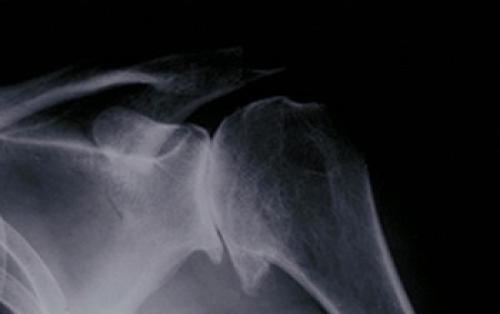

Для уточнения диагноза может быть назначена рентгенография грудной клетки, на которой выявляются аномалии развития, неправильно сросшиеся переломы ребер и лопатки. Для уточнения диагноза может быть назначена компьютерная томография, на которой получается детальное изображение костей в 3D проекции. Если заподозрен бурсит, наиболее ценную диагностическую информацию дает магнитно-резонансная томография.

Для точной диагностики артрита плечевого сустава используют методы рентгенографии и компьютерной томографии.

Если хотите выяснить причину, проведите рентген плечевого сустава и МРТ шейного отдела. Под хрустом в суставах понимают щёлкающие или трескающие звуки, которые они издают при активных либо пассивных движениях.

При наличии клинической картины артроза, артрита, бурсита либо тендинита сустава, необходимо провести рентгенологические либо томографическое (по показаниям) исследование. Также данный признак может свидетельствовать о травме или дисплазии сустава, которая привела к развитию вторичного заболевания.